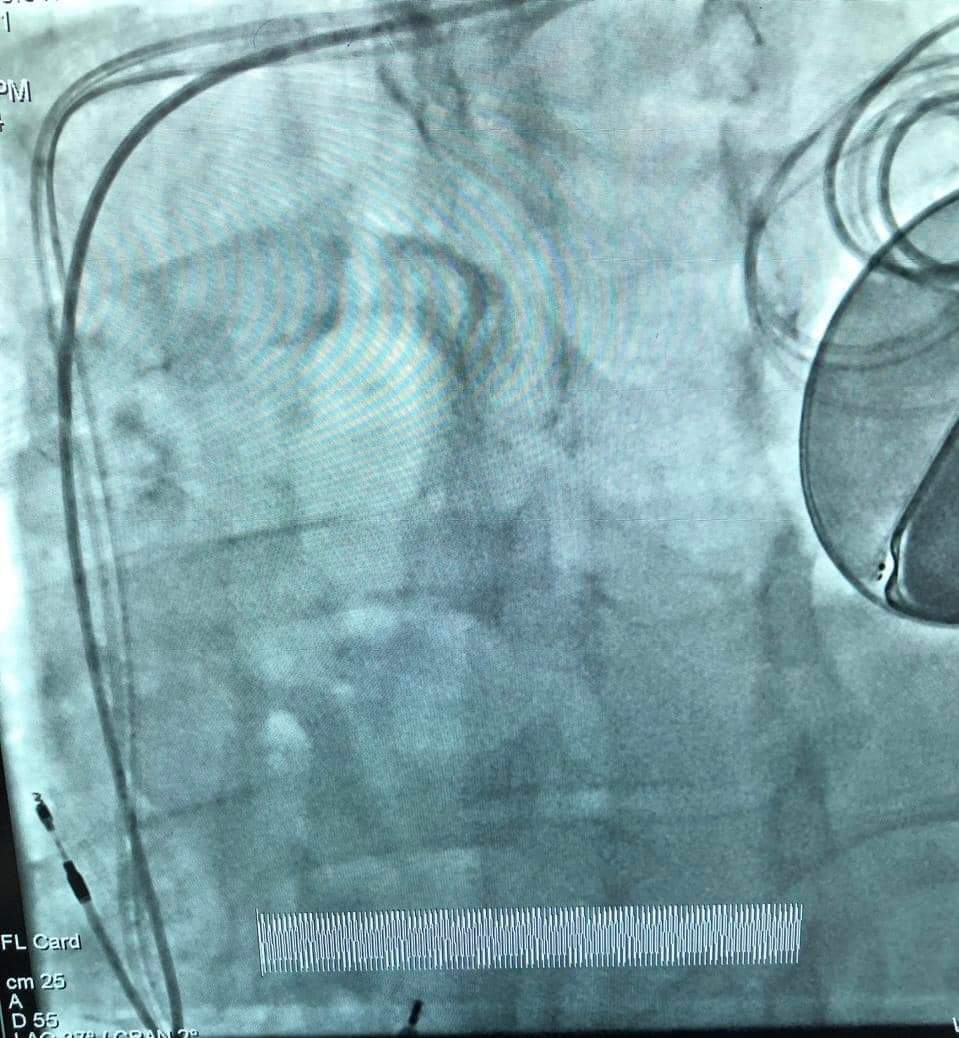

جانب من إجراءات العملية بمستشفى المنصورة التخصصي

أعلن مستشفى المنصورة التخصصي التابع لأمانة المراكز الطبية المتخصصة عن زراعة وتركيب جهاز منظم ثلاثي دائم بصاعق داخلى لأول مرة بقسم القسطرة التداخلية بالمستشفى، حيث قام فريق طبى بقيادة الدكتور هانى عبد الشكور بزرع جهاز CRT - D لمريض يبلغ من العمر 68 عاما، ويعاني من ضعف شديد بعضلة القلب، وتعرض مرات متعددة لخلل فى كهرباء القلب فى شكل تسارع وارتجاف بطينى، وهى حالة عالية الخطورة، ومهددة للحياة.

يساعد هذا الجهاز حجرات القلب على الانقباض بطريقة أكثر تنظيمًا وكفاءة، وهو خيار علاجي لمرضى اعتلال عضلة القلب التوسعي، ورغم الصعوبات الفنية الكبيرة، وخطورة الحالة، تم الإجراء الطبي بنجاح كبير، وتحسنت حالة المريض بشكل كبير.